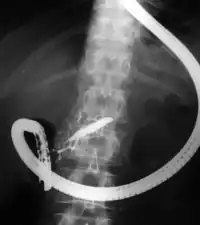

![]() Duodenoscopic image of two black pigment stones extracted from common bile duct after sphincterotomy | |

The patient is sedated or anaesthetized. Then a flexible camera (endoscope) is inserted through the mouth, down the esophagus, into the stomach, through the pylorus into the duodenum where the ampulla of Vater (the union of the common bile duct and pancreatic duct) exists. The sphincter of Oddi is a muscular valve that controls the opening to the ampulla. The region can be directly visualized with the endoscopic camera while various procedures are performed. A plastic catheter or cannula is inserted through the ampulla, and radiocontrast is injected into the bile ducts and/or pancreatic duct. Fluoroscopy is used to look for blockages, or other lesions such as stones.[8][9]

When needed, the sphincters of the ampulla and bile ducts can be enlarged by a cut (sphincterotomy) with an electrified wire called a sphincterotome for access into either so that gallstones may be removed or other therapy performed.[10]

Other procedures associated with ERCP include the trawling of the common bile duct with a basket or balloon to remove gallstones and the insertion of a plastic stent to assist the drainage of bile.[11] Also, the pancreatic duct can be cannulated and stents be inserted.